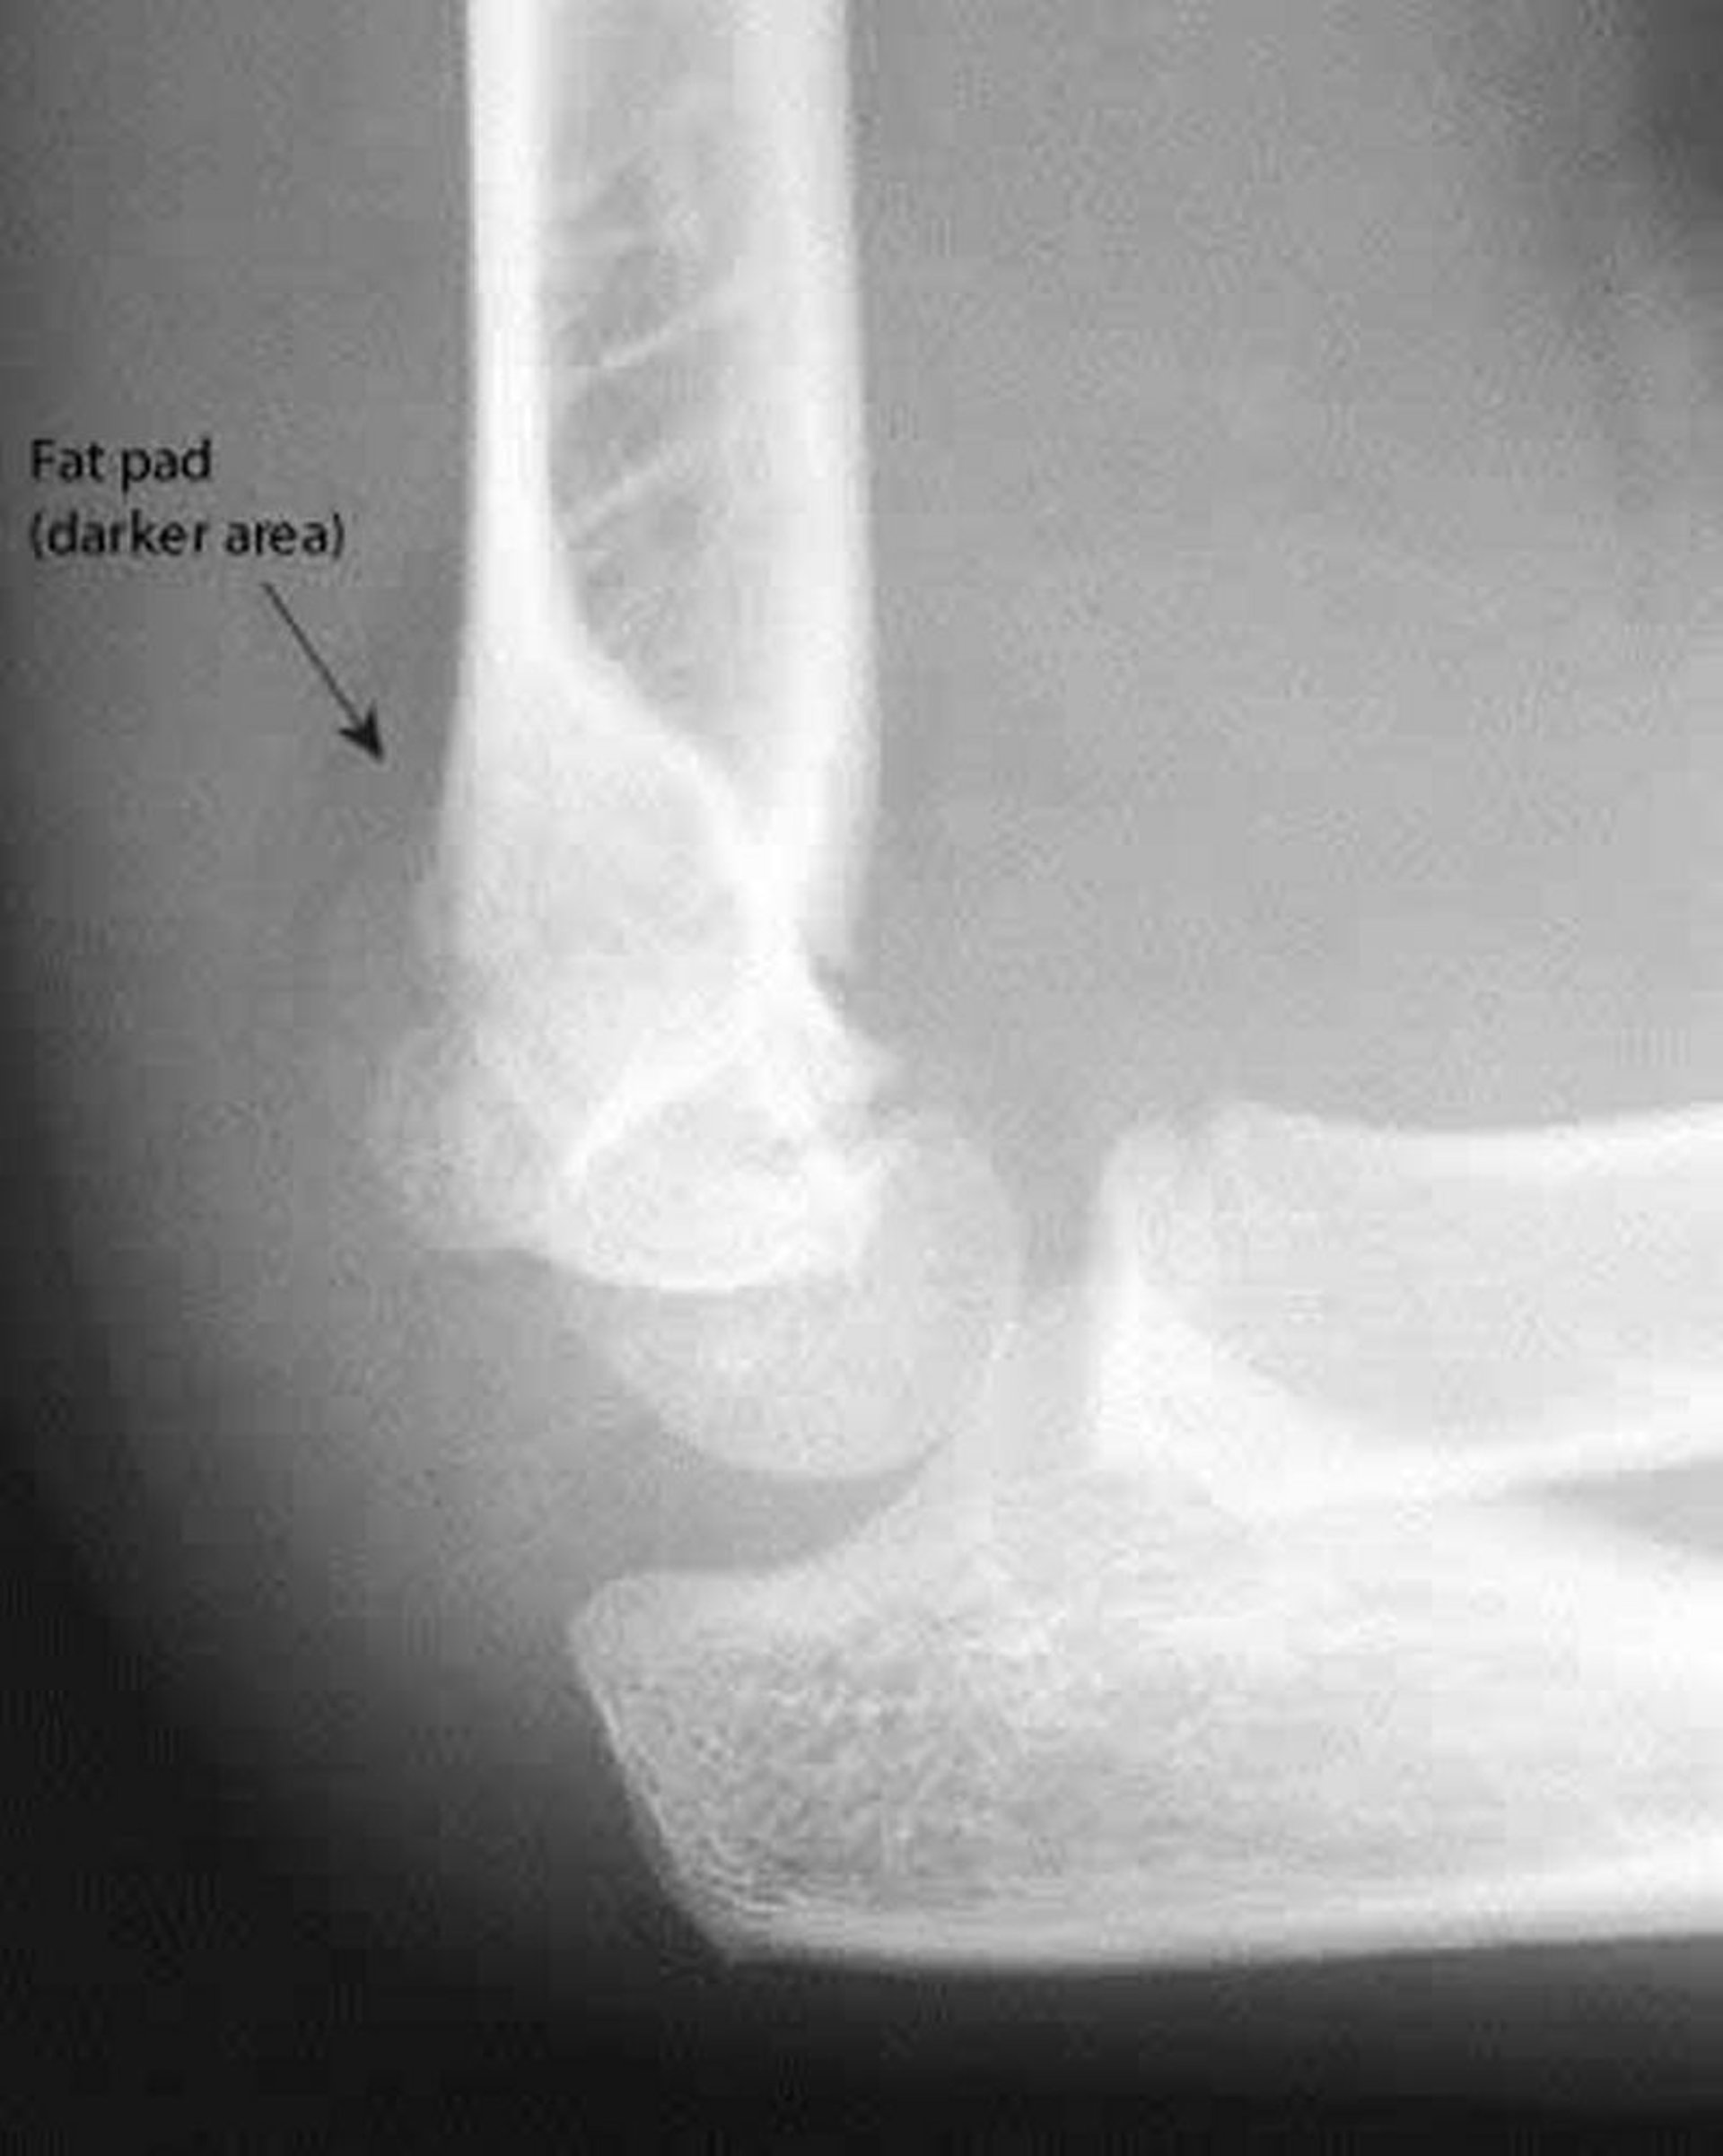

Cuscinetto adiposo posteriore

Un cuscinetto adiposo posteriore è sempre anormale. Anche in questa RX, la linea omerale anteriore non interseca nel mezzo il capitello radiale.